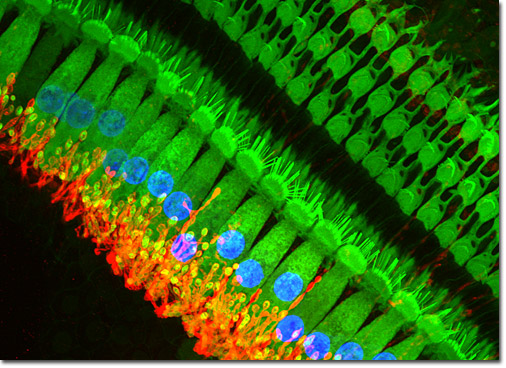

예술적인 현미경 사진이라면 요즘 보통 이런걸 얘기하곤 하죠,confocal microscopy 로 검색하시면 찾으실 수 있습니다.

아래 사진도 구글에서 제가 찾은 것입니다, 물론 이렇게 나오는 건 드뭅니다. 아마 이사진도 시약회사쪽에서 찍은 광고용 사진중 일부일겁니다.

아마도 기관지 상피 세포를 찍은 것 같은데 푸른색은 세포핵, 붉은 색은 세포끝에 붙어있는 섬모(cillia), 그리고 초록색은 세포질과 세포 뿌리에 해당하는 부분입니다.

보통 green-red 조합이 contrast 가 잘되기 때문에 두가지 조합을 가장 많이 사용합니다.

이론상으로는 5가지 이상 조합이 가능하지만 보통 2-3가지 색조합을 많이 사용합니다.

세포나 조직 항원에 눈으로 볼 수 있는 발색제를 붙여서 현미경으로 관찰해서 볼 수 있는 사진인데 형광 발색제를 쓰게 되면 이런 사진을 찍을 수 있습니다.